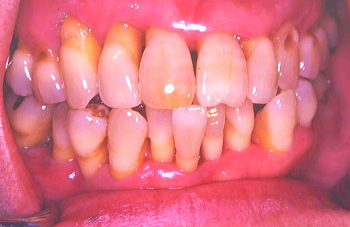

③ 上の前歯は少しぐらぐらするので、歯と歯の間をボンドで止め固定した。患者の熱心な歯磨きにより前回よりいっそう歯肉が引き締まり健康になった。しかし歯周ポケットは深いままなので外科によりポケットを除去しなければならない。この状態は治ったように見えるが、これは見せかけの治癒で本当は完治していない。

④ 外科処置前に上の歯の虫歯治療と6本の歯の動揺(ぐらぐら動くこと)防止目的で歯を削り6本をひとまとめにした仮り歯を入れ、固定しなければならない。